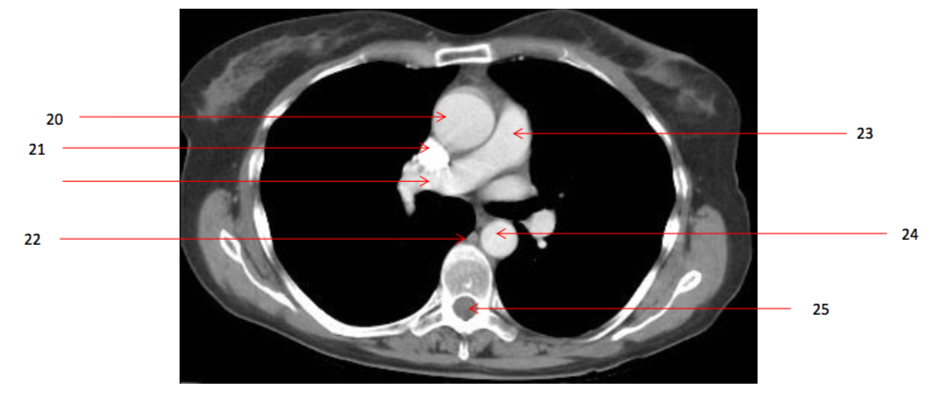

Number 20?

Ascending aorta

Number 21?

SVC

Number 22?

Azygos vein

Number 23?

Pulmonary trunk

Number 33?

Descending thoracic aorta

Number 17?

Number 18?

trachea

Number 36?

Lt atrium